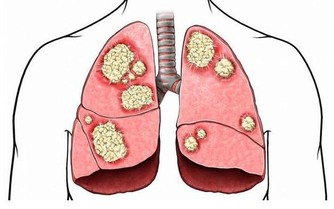

終於找到害她肩背疼痛的「元兇」——胰腺癌。

醫生說,這些症狀已經在提示姚女士胰腺壞了。

胰腺疾病不容易發現,如果能早點注意到發病信號,對治療很有幫助。

他介紹,現代人的飲食結構中,肉、蛋、奶和精細食物增多,蔬菜、粗糧減少,

再加上抽菸、喝酒、吃燒烤等不良習慣,導致胰腺疾病的發病率增多,且逐漸年輕化。

以前,胰腺癌患者基本都是五六十歲以上的人,而現在,30多歲的患者也時而可見。